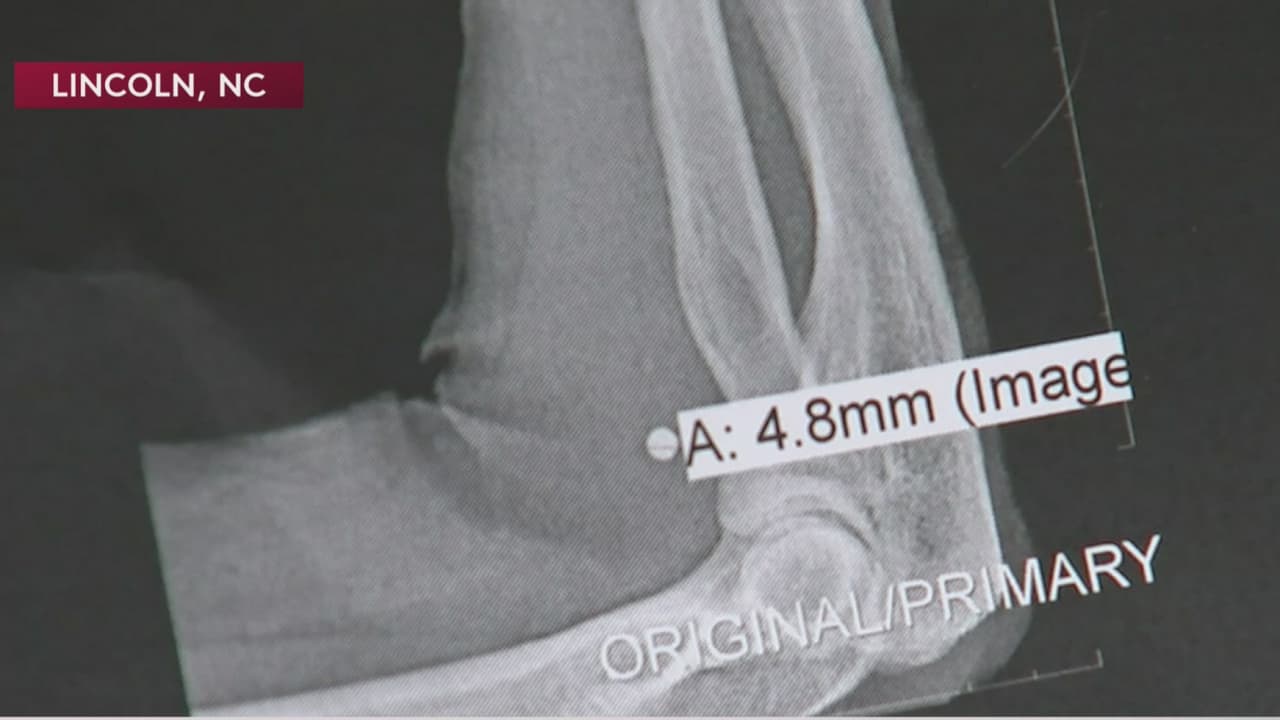

Una mujer de Carolina del Norte retiró un letrero de Trump del jardín de una residencia en Lincolnton. Peggy Fox pensaba que el anuncio de campaña estaba en la casa de su hermano, pero este había sido colocado en la propiedad de Worth McAllister, de 76 años. El hombre afronta cargos por dispararle con un arma de aire comprimido.